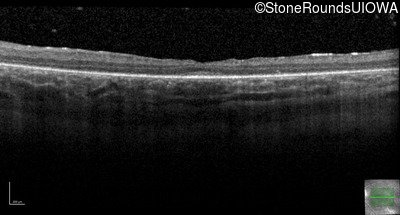

Optical Coherence Tomography - Right - 20/80 -1

Exemplar / OCT Stack

OCT Stack